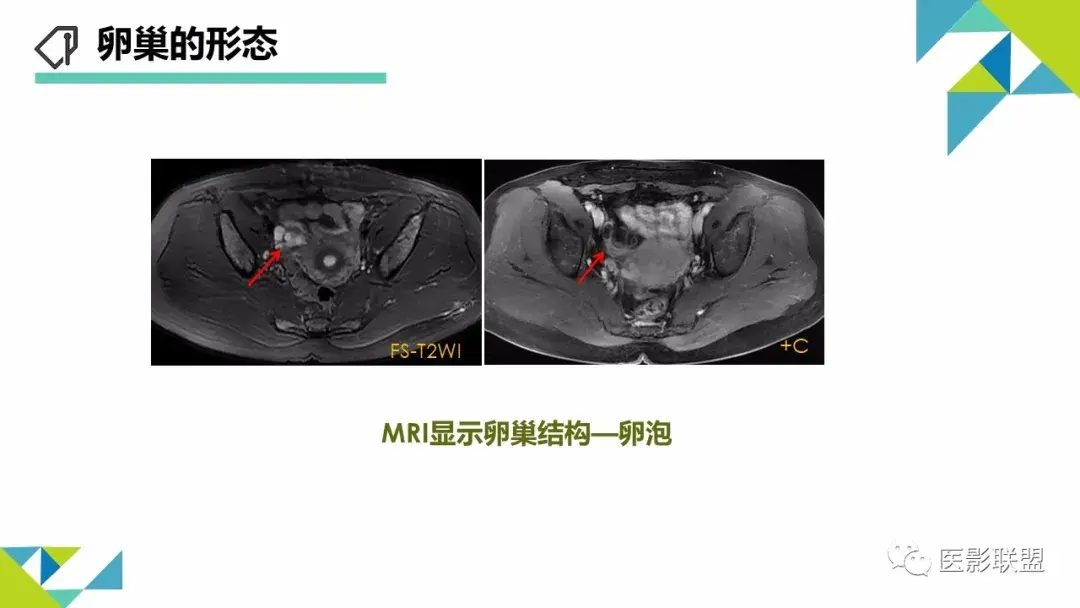

卵巢畸胎瘤的图像诊断及不典型征象分析

作者:刘红艳 清远市人员医院